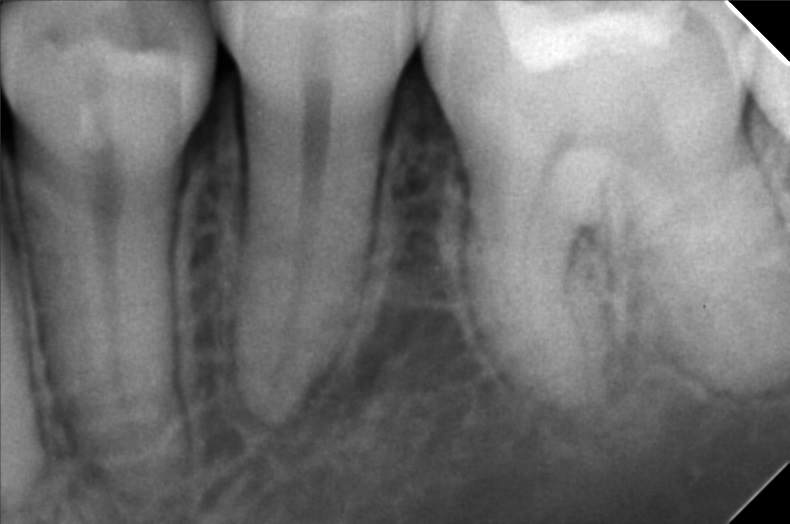

Edit Record Check our patient data records. Add patient information Patient Info Profile picture Last Name First Name Middle Name Birthdate Age Street Barangay City Country Zip Code Contact number Email Procedure 01/16/20 #18 niti lower #41 RW (distal) 09/17/21- exo 16/ upper for removal lower teeth- 34^ 16*16ssL 4/21/22- Implant #16 4.3 x 10mm with sinus lift #36 4x3 x 10mm under Iv CS 09/06/22 peri implantitis/ currettage and debridement/ ozone/ CGC/PRF/ bone filler- bio oss 025g 10/5/22 - CHECK UP; PRESCRIBED VIT D 1000IU; 0.9%NSS; ORAHEX 11/04/22-2healing Ab. 12/13/22- Pick up impression 12/24/22- IntsofCrown 5/06/23- Odontectomy tooth #12/Compound odontoma removal GBR-double oss cancellous and cortical bone 1cc and .25 cc with xenograft .25g/PRF-GTR Trapezoidal flap under IV conscious sedation non resorbable suture-nylon Specimen histopathology 05/20/23- removal of suture/ozone therapy/LC 46 mesial, Occlusal, buccal removal of amalgan 46 06/29/23- check up/xray/rem bal 3200 08/25/23-#12 Build Up/ Lingual retainer/OP 3200 BALANCE USED 04/19/24 check up LC #36 Occlusal of crown #26 lingual pit 05/25/24 3D scanning 10/04/24 #12 4mmx 11.5mm w/ incidental graft 1CGF 3 PRF membrane Odontectomy #38 10/12/24 attachment of temporary teeth 03/14/25 install healing abutment OP 05/01/25 3D scanning #12 full contour top abutment O/D: 5 G/H: 3MM A/H: 8MM 01/31/26 LC#37-B OP w/polish File micheal_2.jpg File 2 micheal.jpg File 3 img_20220421_171028.jpg File 4 300391815_794848065019598_3764074978376967115_n.jpg File 5 301522684_1451524321981960_1833940363743363873_n.jpg File 6 borja-m.jpg File 7 img_20221227_110757.jpg File 8 img_20221227_110831.jpg File 9 1000000484.jpg File 10 img_20241004_153433_742.jpg File 11 File 12 File 13 File 14 File 15 File 16 File 17 File 18 File 19 File 20 Retain Record Retain Record Yes No Save Your Changes